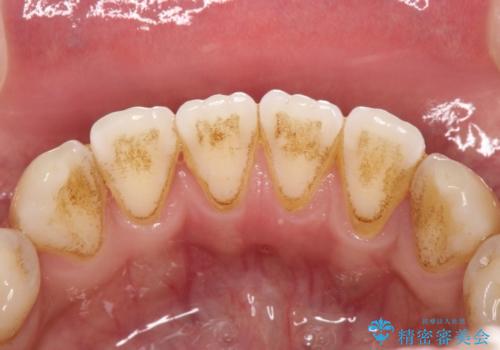

親知らずを抜いて1週間後にPMTC 歯のクリーニング

- 親知らずの抜歯後の約1週間後に抜糸(縫った部分の糸とり)で来院されました。その際、抜歯後は傷口が怖くて歯磨きが上手くできず、汚れや口臭が気になるためクリーニングも希望されました。

抜歯後は多少出血したり、違和感や痛みを感じたりすることがあります。そのため親知らずを抜いたり、外科的な処置をするといつも通りの歯磨きがしづらくなります。また、傷口の周りが心配で、歯ブラシをするのが怖くなるものです。抜歯後落ち着いたら、歯科医院にて専門の機械を使用しクリーニングをすることがおすすめです。抜歯前や後にPMTCを行うことで、お口の中の健康維持につながり、その後の感染・腫れ・口臭予防などになります。

親知らず抜歯後正常に治癒が進んでいれば1週間後から可能です。